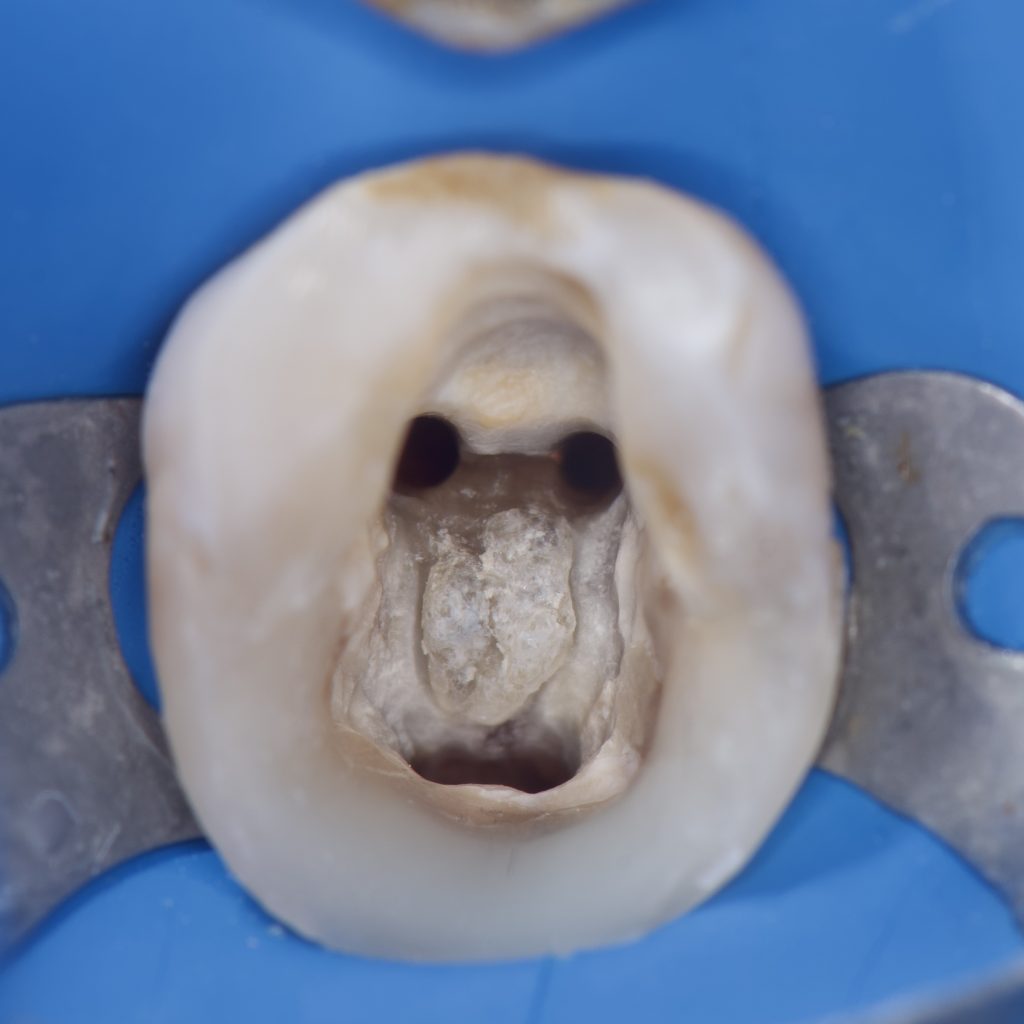

– Treatment began with removing the old amalgam filling and cleaning the tooth from the remaining caries and excess Gutta percha